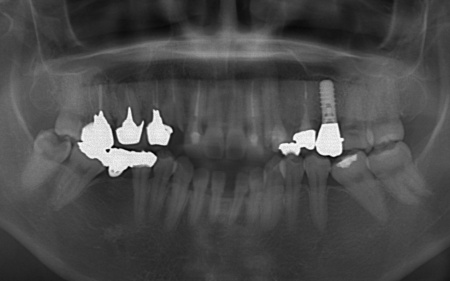

40代女性 矯正治療で噛み合わせを整えたあとセラミックの被せ物・詰め物で修復した症例

「左下の奥歯が欠けたのと、右上の差し歯が取れた」とご相談いただきました。

拝見したところ、左下と右上の歯はともに大きな虫歯があり、歯だけでなく被せ物を支える土台の部分にも影響が及んでいました。

さらに、ほかの歯に入っている詰め物や被せ物の周囲にも、過去に治療した部分に再び虫歯ができる二次カリエスが複数見つかりました。

また、噛み合わせを確認したところ、奥歯で噛み合わせた際に上下の前歯が当たらず隙間ができる開咬(かいこう)が認められました。

なお、左上の奥歯には人工歯根を埋め込んで失った歯を補うインプラントが装着されていたものの、人工歯根の位置や骨との結合状態に問題はありませんでした。